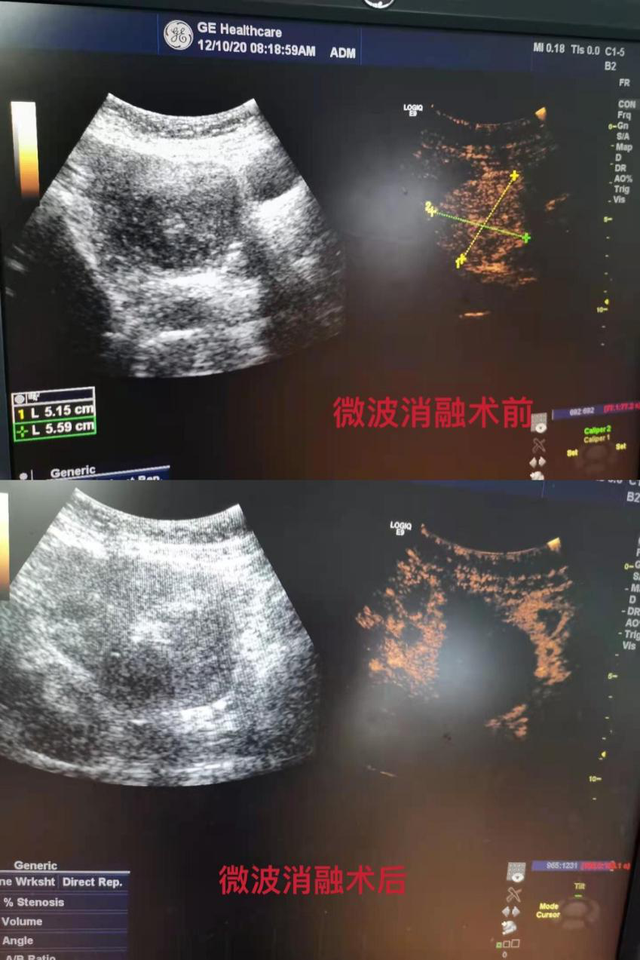

近日,陈女士孕前检查发现一个8*7cm子宫肌瘤,辗转多家医院,尝试了各种治疗方法,效果都不明显。在朋友的建议下,陈女士来到南昌市第三医院抚河院区妇产科就诊,B超显示,她的子宫肌瘤增大明显已压迫宫腔使之变形,可能影响受孕。这下她犯愁了:“这个肌瘤到底要不要手术?是先生孩子还是先做手术?子宫肌瘤会不会影响怀孕?”考虑到该患者年轻,想备孕二胎,有生育要求,又想不做手术消除子宫肌瘤,综合考虑患者需求下,经充分讨论,蒋冰主任团队决定对其采取子宫肌瘤微波消融术。

微波消融术为极微创手术,在超声引导下通过消融针经皮进入子宫病变处,进行热疗使病损部位组织灭活,然后逐步吸收、缩小,从而达到治疗的目的,对子宫基底层及卵巢功能无影响,不需开腹,完整保留了子宫与盆腔结构的完整性,是妇科微创史中又一新的突破。